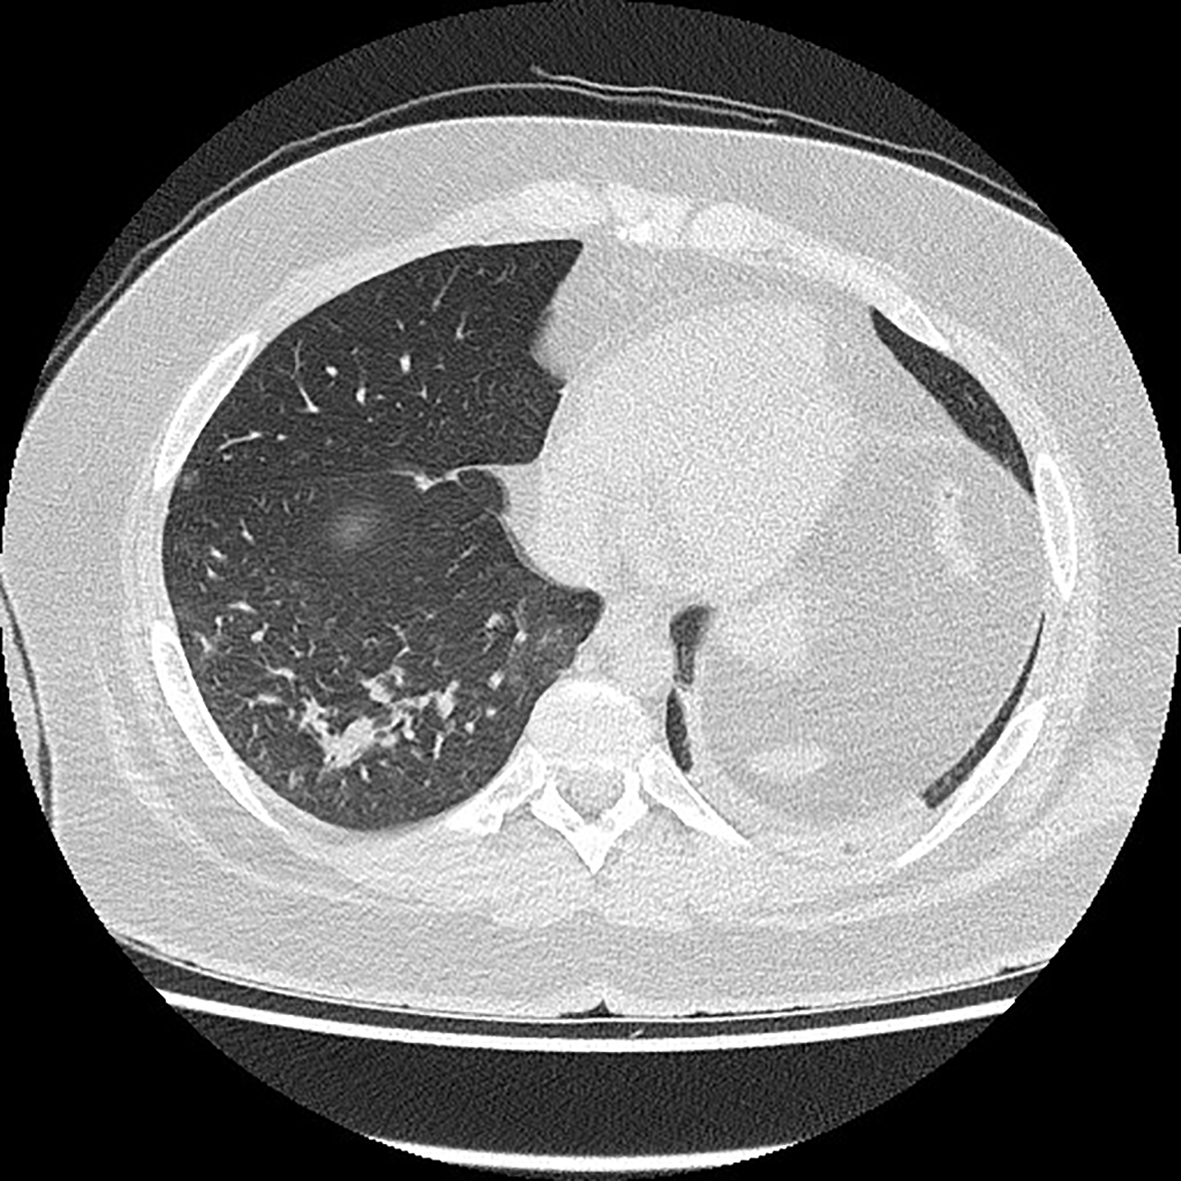

A 22-year-old patient without chronic diseases was admitted to the Department of Thoracic Surgery to establish diagnosis of mediastinal tumor. The first symptom of the disease was pathological fracture of the right arm. On admission, the patient’s performance status was good (ECOG score 1); he had no symptoms of infection. He complained of mild chest discomfort and hyperhidrosis, without fever. He denied dyspnea, cough, weight loss, loss of smell and taste. Blood oxygenation was normal (97%). Laboratory tests showed no abnormalities in peripheral blood count (WBC 7.27x109/L, HGB 10.7 g/L, PLT 273 109/L), but there was elevated level of LDH (1650 U/L). SARS-CoV-2 molecular nasal swab test before thoracorurgical procedure was negative. He had a biopsy of the mediastinal tumor, which confirmed primary mediastinal B-cell lymphoma (PMBCL): large B-lymphocytes, CD20+, CD23+/-, CD 30+/-, BCL6+, c-myc+, BCL2+ (double expressor), cyclD1-, Ki67 80%. Computed tomography scan revealed mediastinal tumor infiltrating thoracic wall, ascending aorta, pulmonary trunk. There were found two satellite tumors, 17 mm in diameter, in segments 4, 5 and 6 of the right lung; lymphoma tumors in the pancreas, pelvis, 10th right rib and proximal end of right humerus with pathological fracture. There was no lymphadenopathy detected. Active lymphoproliferative process was confirmed also in positron emission tomography scan (PET CT). The diagnosis was made of PMBCL stage IV according to Ann Arbour classification, aaIPI (age-adjusted international prognostic index) high intermediate (3 points). It was decided to perform orthopedic surgery of the pathological fracture and then to start chemotherapy. The SARS-CoV-2 molecular test was carried out before orthopedic treatment and it was positive. Date of positive SARS-CoV-2 test (twelve days after admission to hospital) suggests that hospital transmission of SARS-CoV-2 infection was the most probable. The patient was still in good performance status, without acute symptoms of COVID-19. There was no cough or fever detected. In the next CT scan (Figure 1), ground glass opacities in about 15% of the lungs were described – a typical imaging feature of SARS-CoV-2 infection. The patient was complaining of mild constant chest discomfort, but this symptom was present before SARS-CoV-2 infection and most probably caused by the presence of tumor mass in the mediastinum. Because of advanced stage PMBCL, it was decided to start lymphoma’s pretreatment. The patient was treated with 5-day regimen of cyclophosphamide 200 mg/m2/day and prednisone 40 mg/m2/day. We did not observe acute tumor lysis syndrome after this therapy. Laboratory tests showed normal level of LDH. Patient tolerated pretreatment very well without any side effects. No additional symptoms of SARS-CoV-2 infection appeared. Another SARS-CoV-2 test was also positive. It was decided to treat patient with chemotherapy according to CHOP-14 regimen (cyclophosphamide 750mg/m2, doxorubicin 50mg/m2, vincristin 1,4mg/m2, prednisone 40mg/m2). It was decided against the use of rituximab due to the risk of negative effect on SARS-CoV-2 infection. Chemotherapy was supported by G-CSF (filgrastim) administration and prophylaxis of tumor lysis syndrome. After two cycles of chemotherapy partial response of the lymphoma was observed in a CT scan. The patient complained of increased chest discomfort and tachycardia was detected. There were no abnormalities in ECG. Echocardiography examination showed myocardial injury with generalized hypokinesis and decreased ejection fraction (EF) of 45%, aortic valve regurgitation and tachycardia. Biochemical markers of myocardial injury – troponin I, NTproBNP and CK-MB mass – were within normal values. Cardiac drugs were administered (ACE inhibitor, beta-blocker) with good treatment results. The third and fourth cycles of chemotherapy were administered, with liposomal doxorubicin (Myocet) replacing doxorubicin in CHOP-14 regimen. The next SARS-CoV-2 test was negative. The patient is still continuing treatment with chemotherapy, since 4. cycle with rituximab (R-COMP).

Figure 1

Chest computed tomography scan.